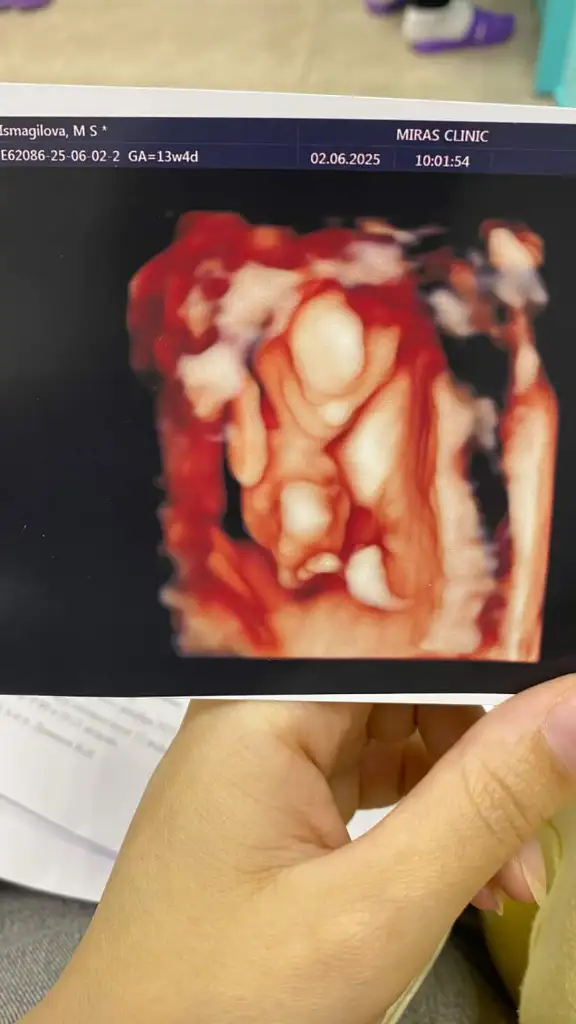

Banada bakarmisiniz rica etsem

Eklentiler

• ED14ED8D-6432-4BB9-B226-217E8AAB082C.webp

ED14ED8D-6432-4BB9-B226-217E8AAB082C.webp

21,6 KB · Görüntüleme: 61

• D69B6048-CB8B-41AD-8947-76B43917AE9E.webp

D69B6048-CB8B-41AD-8947-76B43917AE9E.webp

40,9 KB · Görüntüleme: 41

• 2A0429B6-F556-40BC-AC67-37C9C155B5CE.webp

2A0429B6-F556-40BC-AC67-37C9C155B5CE.webp

40,9 KB · Görüntüleme: 42

• C8C4CFD0-0BF0-43C1-A38A-57C4A7D62568.webp

C8C4CFD0-0BF0-43C1-A38A-57C4A7D62568.webp

19,5 KB · Görüntüleme: 48